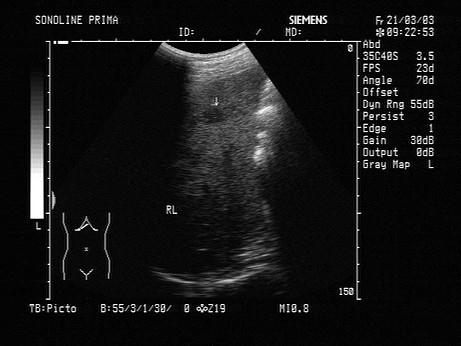

男,49岁,肥胖,血脂增高。结合超声声像图诊断为?(?)A.炎性假瘤B.非均匀性脂肪肝C.肝硬化D.肝结节病E.肝炎

问题 男,49岁,肥胖,血脂增高。结合超声声像图诊断为?(?)

选项 A.炎性假瘤 B.非均匀性脂肪肝 C.肝硬化 D.肝结节病 E.肝炎

答案 B